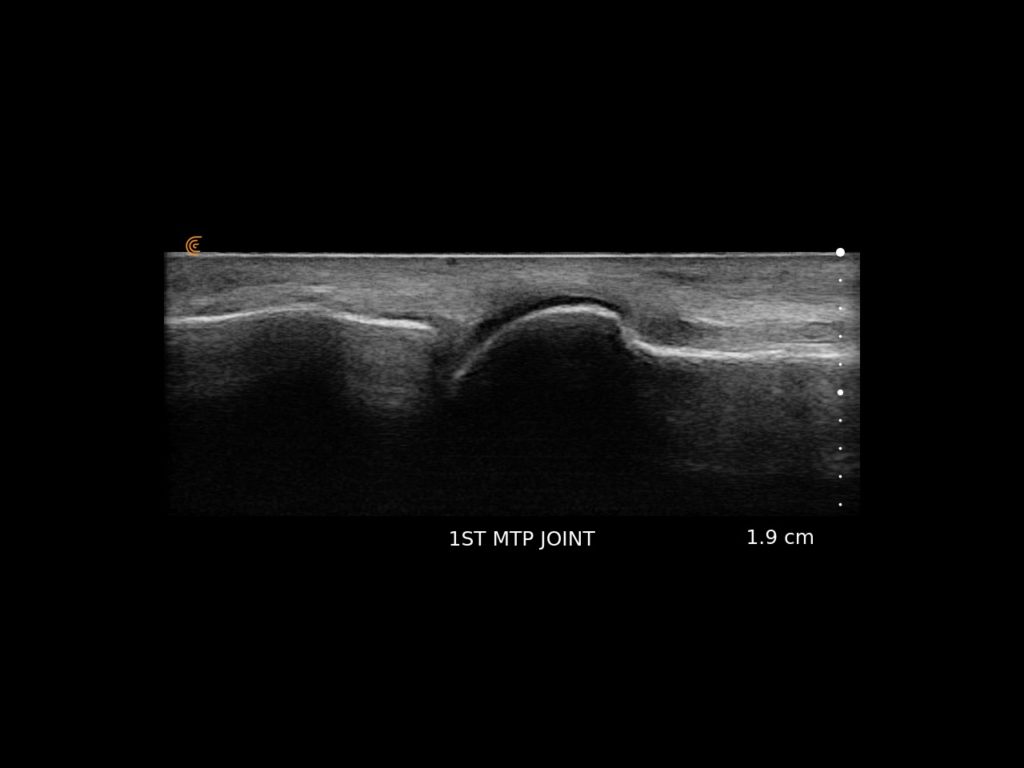

Clarius HD3 is the ideal wireless ultrasound scanner for musculoskeletal (MSK) imaging and procedural guidance. Make a confident diagnosis with high-resolution imaging of muscles, joints, ligaments, tendons, and cartilage both at rest and in motion.